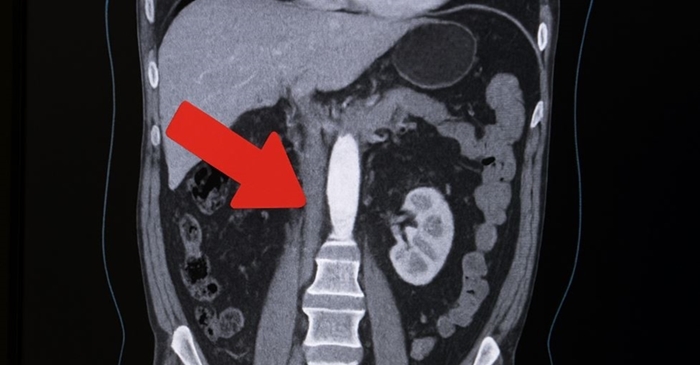

이 병의 진단에는 자기공명영상(MRI) 촬영이나 초음파 검사 등이 필요할 수 있다. 증상을 방치하면 하체에 만성통증 등 노화 징후가 훨씬 더 일찍 나타날 수 있다.